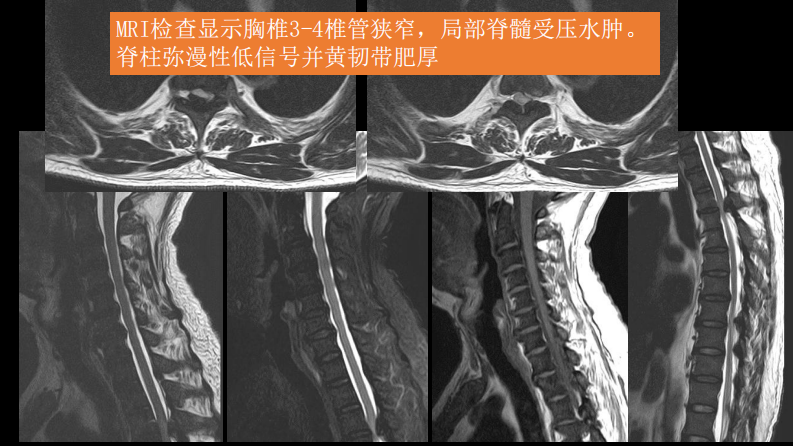

氟骨症的X线CT及MR影像及解读.pdf